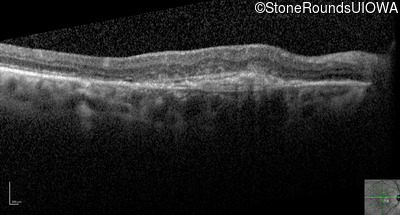

Optical Coherence Tomography - Left - 20/30

Exemplar / OCT Stack

Infrared Fundus Photograph - Left - 20/30

Exemplar